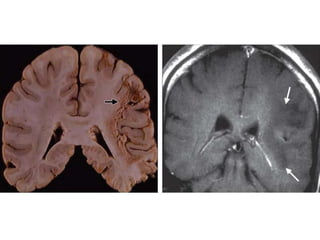

Imagenes

• Atrofia cerebral

simetrica .

• Baja atenuación de

sustancia blanca

en region

periventricular.

• Surco y venticulos prominentes que muestran la atrofia generalizada y

simetrica.

• No efecto masa.

Imagenes • Atrofia cerebral simetrica . • Baja atenuación de sustancia blanca en region periventricular.

• Surco yventiculos prominentes que muestran la atrofia generalizada y simetrica. • No efecto masa.